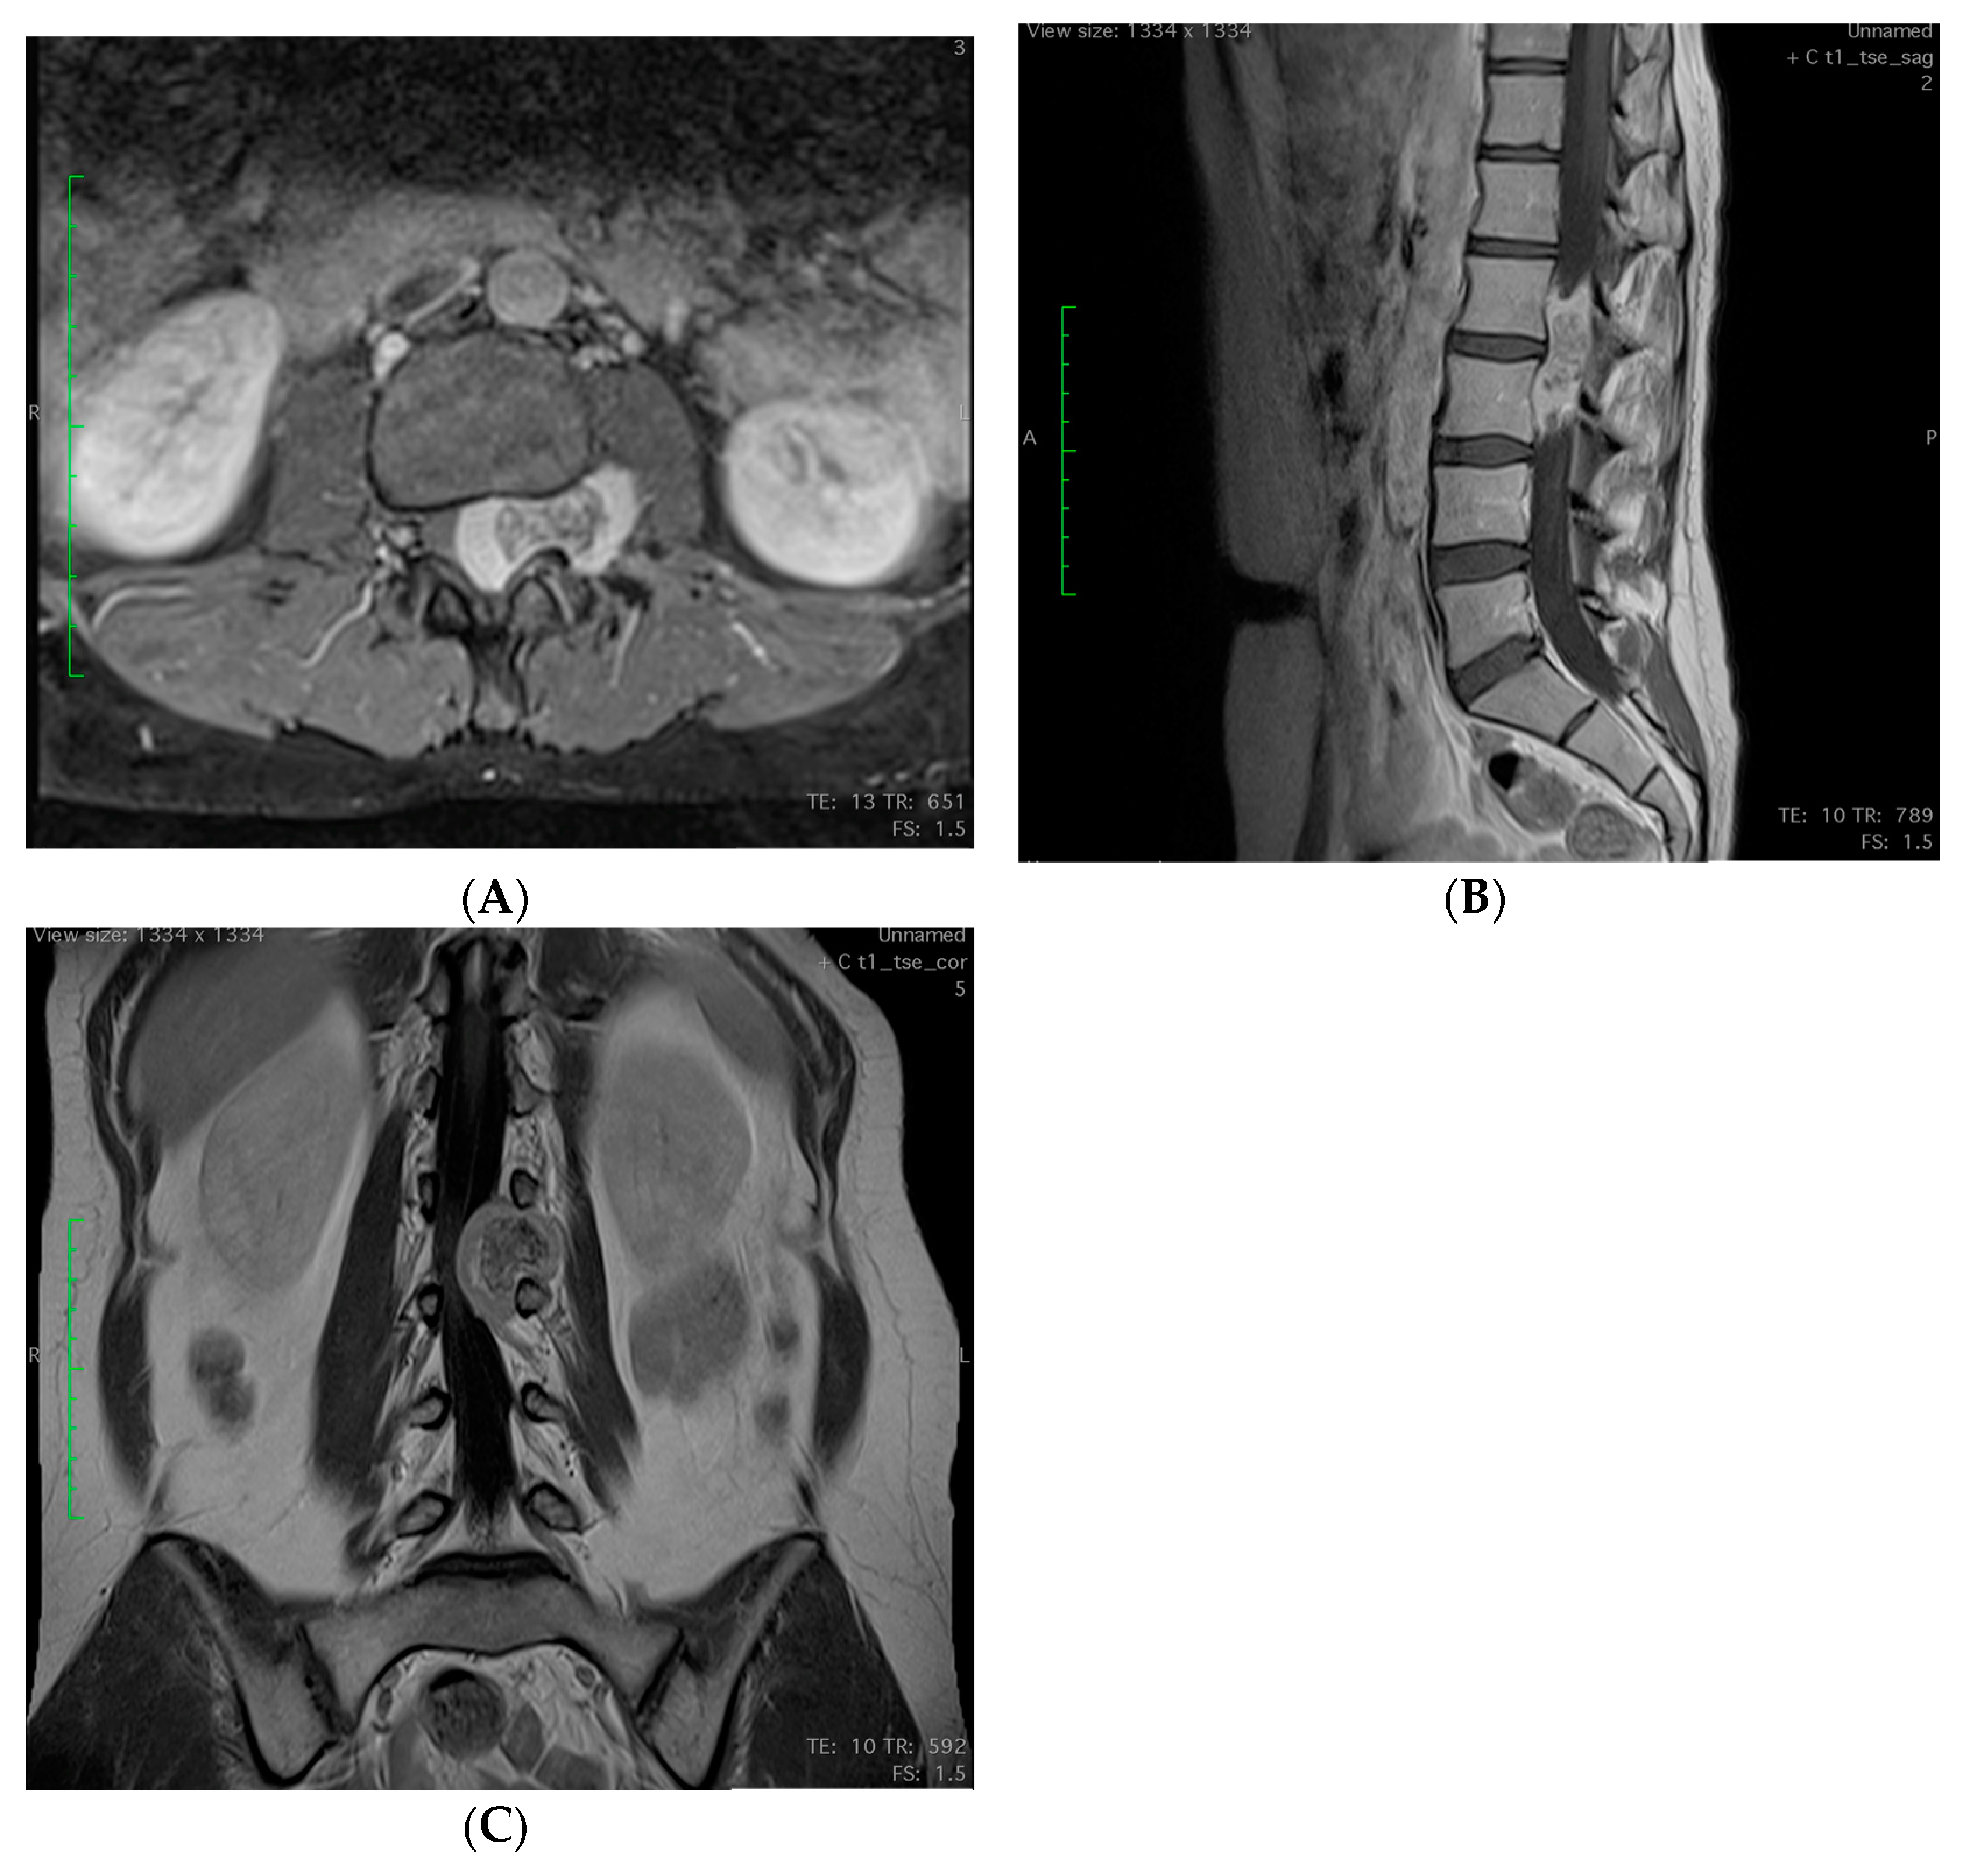

2.3. Imagining